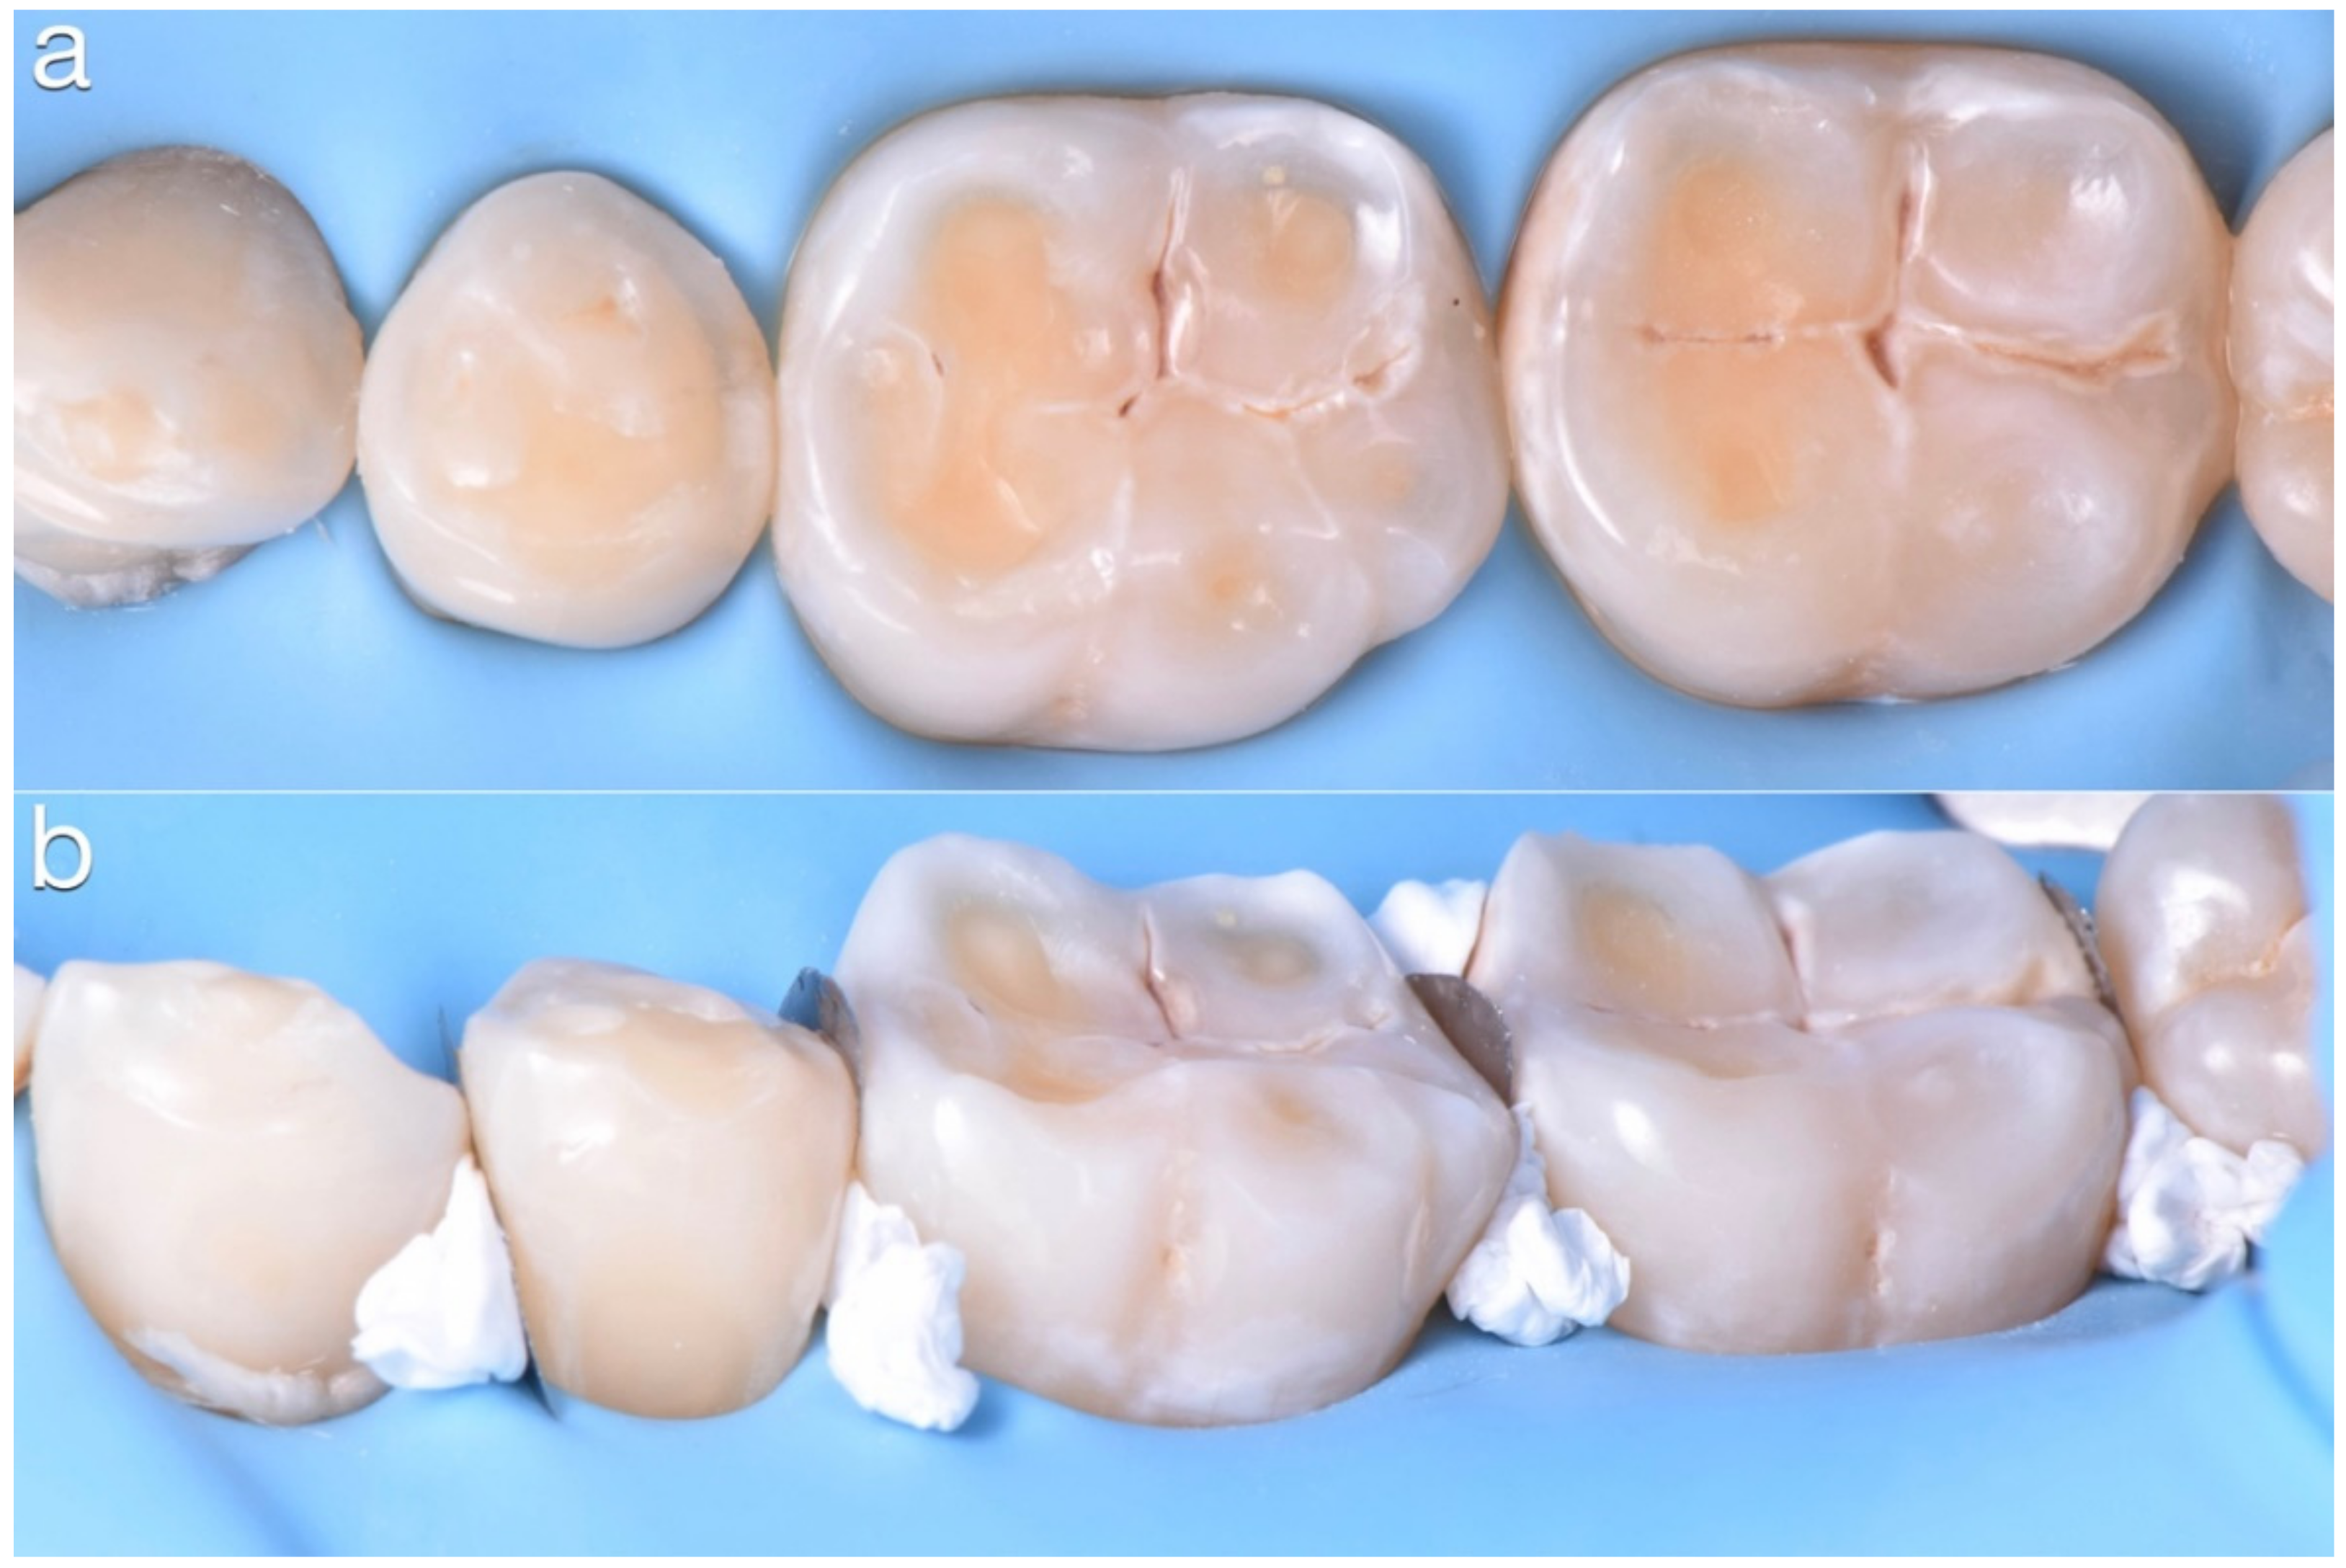

2.2. Restorative Phase